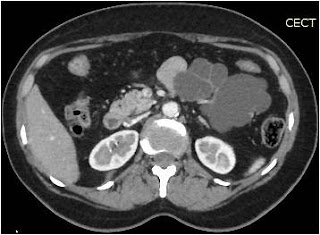

Figure A: Contrast enhanced abdominal computed tomography scan

In our patient, the contrast enhanced abdominal computed tomography scan shows a lobulated cystic neoplasm with septations in the body and tail of pancreas with thin (< 2 mm) non enhancing walls. The cystic spaces (6 in number) are > 2 cm (Figure A). These findings are better appreciated in contrast enhanced abdominal magnetic resonance imaging scan (Figure B). At magnetic resonance cholangio-pancreatography (MRCP), the main pancreatic duct (MPD) is not dilated in its entire course and there was no duct – cyst communication (Figure C). Hence a diagnosis of SOA was made.3